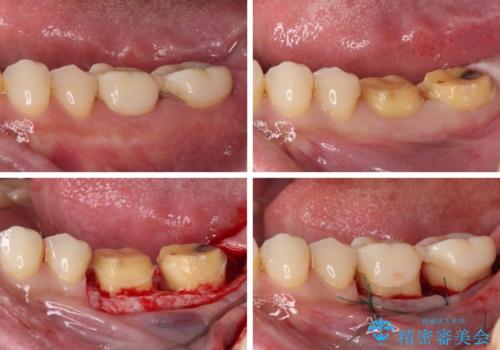

奥歯の歯間部の歯肉が炎症で赤黒くなっており、歯周ポケットを検査したところ、6-8mm(正常では3mm以下)であり、外科処置が適用となる状態でした。

まずは仮歯に置き換え、歯周ポケットを除去するための外科処置(歯肉弁根尖側移動術)を行い、治癒を待ってセラミッククラウンにて補綴治療を行うこととしました。